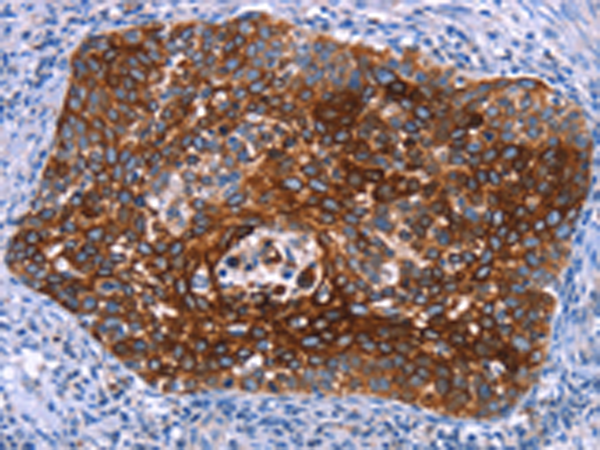

分类: 科研抗体货号: P04318别名: HIP8; HYPD; CT1.3; MAGE3; MAGEA6应用: WB,IHC反应种属: Human